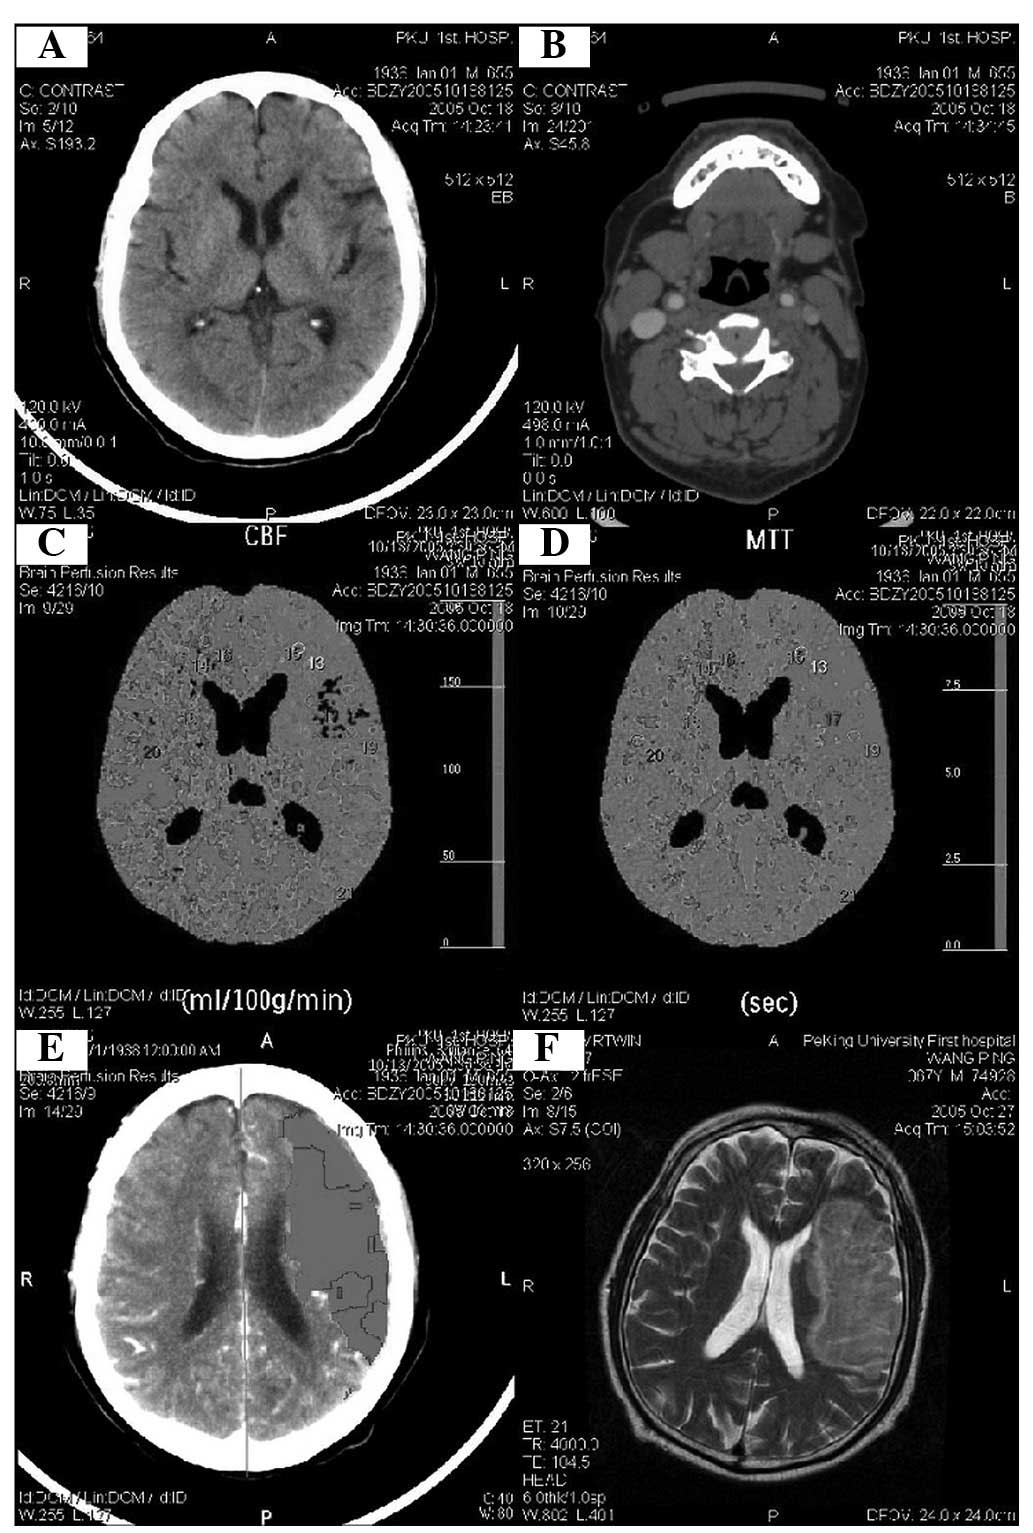

Figure 2.

Case 2, male, 67 years old. Language was not fluent and the mouth/nose was skewed when admitted into hospital. The patient presented mixed aphasia with a consciousness trance-like state for 3 h and the right pathology was weak positive. The plain computed tomography (CT) scan revealed that a lacunar infarct occurred in the left frontal hemisphere, head of the left caudate nucleus and the left radiation crown area. However, CT perfusion identified large areas of ischemia in the left hemisphere and a small infarction area in the middle hemisphere. Two days later, limb function gradually accelerated, until complete paralysis and aphasia occurred. (A) New cerebral infarction in the head of the caudate nucleus. (B) Bilateral carotid atherosclerotic stenosis on the left (50%) and right (30%). (C and D) The cerebral blood flow (CBF) ratio around the lesion core of the left hemisphere was <0.2 indicating irreversible ischemic infarction and the area surrounding the core was considered the ischemic penumbra. (E and F) The infarct area was observed after <3 days using magnetic resonance imaging (MRI).